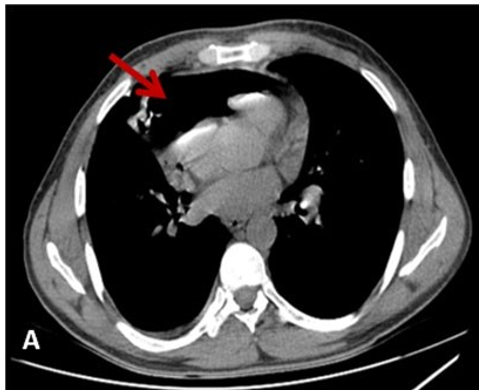

A 64 years old man with a past medical history of a lung cancer undergoing chemotherapy was admitted in the cardiology de- partment for progressive onset of dyspnea. Initially, there were no signs of cardiac tamponade. Transthoracic echocardiography showed the air gap sign, identified as the loss of signal during the systolic phase and the ‘swirling bubbles sign’ several very small bright echogenic spots in the pericardial sac. For better visual- ization, a thoracic computed tomography (CT) was performed and found a right pulmonary mass of with many small areas of gas and a pneumocardium of 24 mm of maximum thickness is shown in the Figure A and Figure B.

Figure: Cardiac Air Tamponade as a Complication of Pulmo- nary Mass

A: CT Scan showing a Massive Pneumopericardium (Red Ar- row)